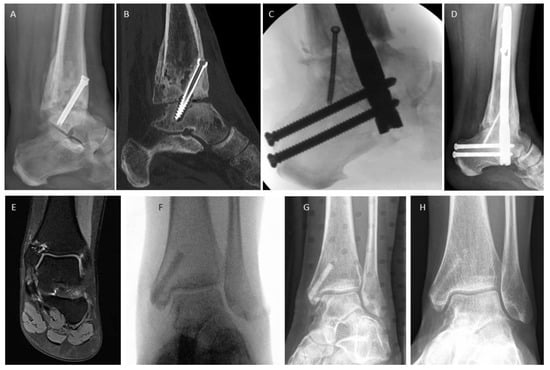

3.4. Examples for Bone Healing

3.6. Radiological Findings of Interest